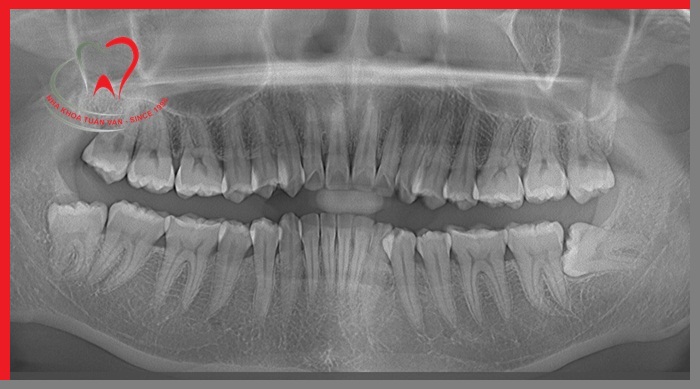

Bước 1: Thăm khám cấu trúc răng cần nhổ và kiểm tra sức khỏe răng miệng

Bác sĩ sẽ tiến hành thăm khám, chụp X - Quang để xác định chiều dài, hình dạng, vị trí và tình trạng xương xung quanh vị trí răng cần nhổ. Từ đó, bác sĩ ước tính mức độ khó của ca tiểu phẫu và hướng nhổ răng hợp lý nhất.

4. Chụp phim khảo sát trước khi nhổ răng

Trước khi thực hiện nhổ răng, các bác sĩ tại Nha khoa Tuấn Vân sẽ tiến hành thăm khám và chỉ định chụp phim X – quang trước. Việc thực hiện chụp phim khảo sát giúp bác sĩ xác định chính xác vị trí, hướng mọc, hình dáng của răng, xác định được hình thể cũng như số chân răng. Qua phim X – quang, bác sĩ sẽ tiên lượng được độ khó dễ của răng và đưa ra phương pháp nhổ răng phù hợp, an toàn với từng trường hợp.